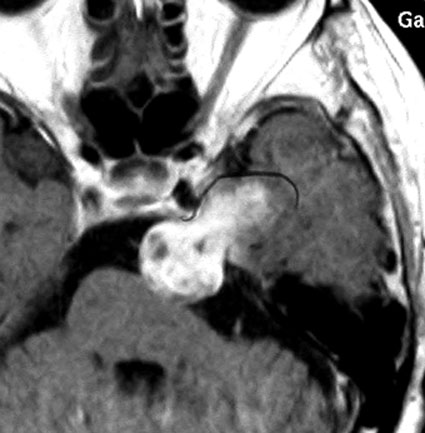

特殊な蔓状三叉神経鞘腫

NF-1ではない孤発例の三叉神経蔦状神経鞘腫です。眼窩内,上眼窩裂,メッケル腔,小脳橋角槽まで伸びる大きなものです。内視鏡の手術はできないので,開頭手術になりますが,全部まとめて摘出できます。